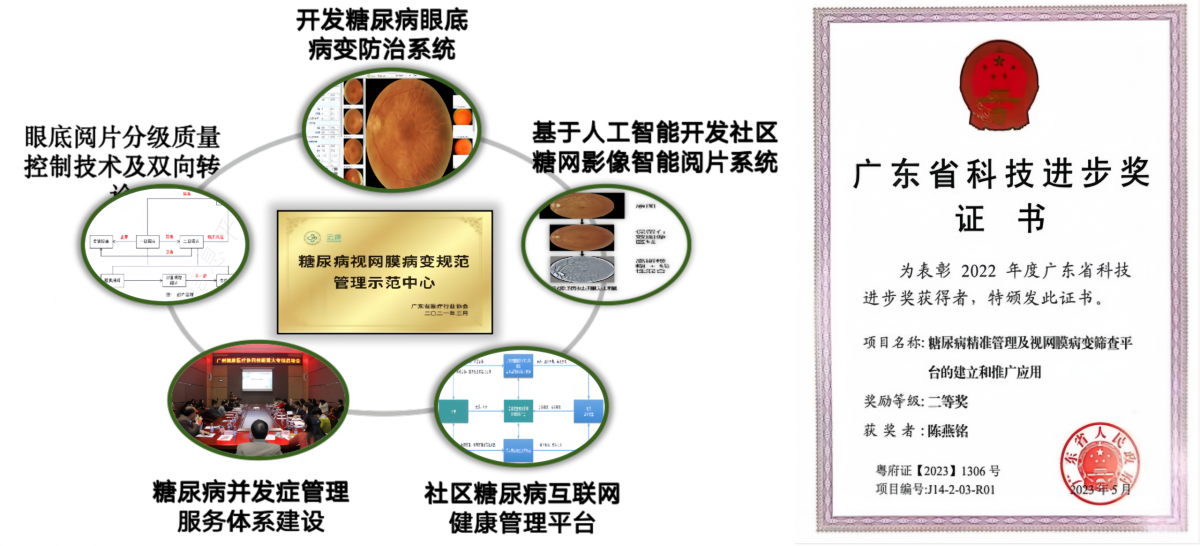

★糖尿病血管并发症早期筛查和管理平台

通过产学研用结合,建立了糖尿病视网膜病变的筛查队列,构建了糖尿病社区互联网健康管理平台。平台开发了人工智能质控与阅片算法,实现基层拍照、远程诊断全流程服务,并集成免散瞳照相、智能诊断软件及云端阅片质控系统。该平台推广至广州市内15家医疗机构、全国100多家社区医院,已为8万多人次提供了眼底免费筛查和健康教育。

通过平台运行,使患者自我管理率从16.6%上升到33%,视力损伤风险显著降低,年人均用于糖尿病及糖尿病视网膜病变、糖尿病肾病等并发症治疗费用降低 33.25%,成果荣获2023年广东省科技进步奖二等奖。

◆创新人工智能驱动的糖尿病精准诊疗技术,革新疾病管理模式;

◆研发智能视网膜影像诊断系统,建设糖尿病微血管并发症早筛平台;